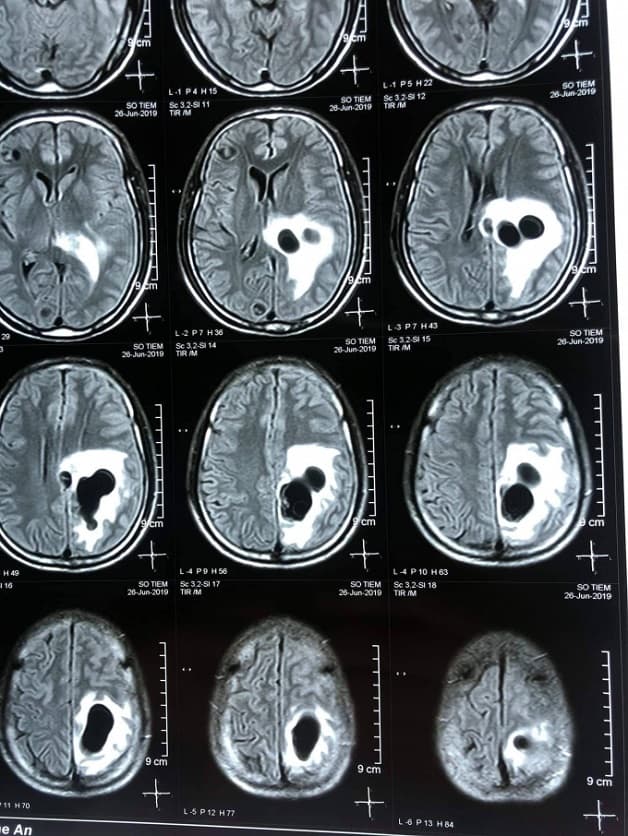

Chụp CT hay chụp cắt lớp vi tính sọ não là phương pháp chẩn đoán cận lâm sàng dùng tia X để tái tạo hình ảnh giải phẫu phần đầu và mặt.

Các hình ảnh của vùng đầu – mặt bao gồm: não, mắt, xương mặt, hệ thống xoang (khoang chứa khí trong xương gần mũi), tai trong. Chính vì vậy, chụp cắt lớp vi tính sọ não được dùng để đánh giá các bệnh lý liên quan đến các bộ phận này.

Chụp CT sọ não là phương pháp chẩn đoán hình ảnh giúp nhận diện các tổn thương ở vùng đầu, mặt.

Chụp sọ não bằng phương pháp cắt lớp vi tính giúp chẩn đoán các bệnh lý nhiễm trùng, khối u, các chấn thương ở sọ não.